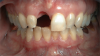

An example illustrating the manner in which these factors are considered in case selection, implant placement, and implant restoration is the case of a female patient who presented with a missing central incisor, tooth No. 8 (Figure 1 and Figure 2). While this example presents an ideal situation for a single implant-supported restoration, analysis is required to determine the appropriate implant width and length, presence of adequate bone, quality and quantity, soft-tissue health, abutment type (ie, custom or stock), and restoration type (ie, cement- or screw-retained).

Fig 1. A female patient presented missing tooth No. 8, which would be replaced with a single implant restoration.

Figure 1

Fig 2. The ridge was of adequate size and dimension, so a 4.3-mm implant was selected.

Figure 2